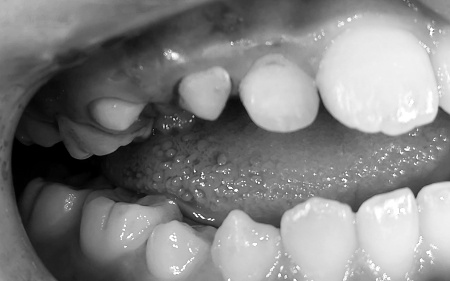

60代女性 歯根が割れて痛む歯を抜いてインプラント治療で噛み合わせを回復した症例

- 骨再生

- ホワイトニング

- 詰め物・被せもの

- オフィスホワイトニング

- セラミック・ジルコニア

- インプラント

- 歯科口腔外科

- ソケットリフト

- 抜歯

- 治療期間の目安 1年2ヶ月

治療費総額の目安

約899,000円

(インプラント治療・オフィスホワイトニング)

治療のリスク

・外科手術のため、術後に痛みや腫れ、違和感を伴います ・メンテナンスを怠ったり、喫煙したりすると、お口の中に大きな悪影響を及ぼし、インプラント周囲炎などにかかる可能性があります ・糖尿病、肝硬変、心臓病などの持病をお持ちの場合、インプラント治療ができない可能性があります ・高血圧、貧血・不整脈...